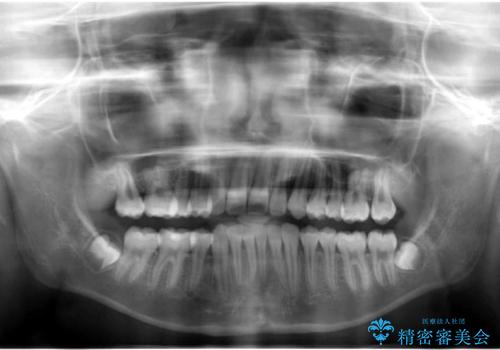

埋まっている犬歯を抜歯して、歯列矯正

- 右上の犬歯が埋伏していたため、抜歯しました。

その後、右下の小臼歯を1本抜歯し、ワイヤー矯正を行いました。

犬歯の代わりに小臼歯を配列し、最小限の抜歯の本数としました。

犬歯の両側の歯に関しては移動することにより歯槽骨が順調に回復し、上顎洞底の形態にかかわらず歯根のパラレリングを行うことができました。

犬歯の両側の歯に関しては移動することにより歯槽骨が順調に回復し、上顎洞底の形態にかかわらず歯根のパラレリングを行うことができた理由としては、年齢が10代前半と若かったからだと思います。

左上4−7については、近心傾斜をしていたため、右上3を抜かずに遠心に移動して非抜歯で治療を行う案も提案しましたが、抜歯を選択されました。結果的に深く埋まっていた右上犬歯を牽引せずにすみ、さらに歯根の向きも整えることができてよかったです。治療も比較的短期間で済みました。